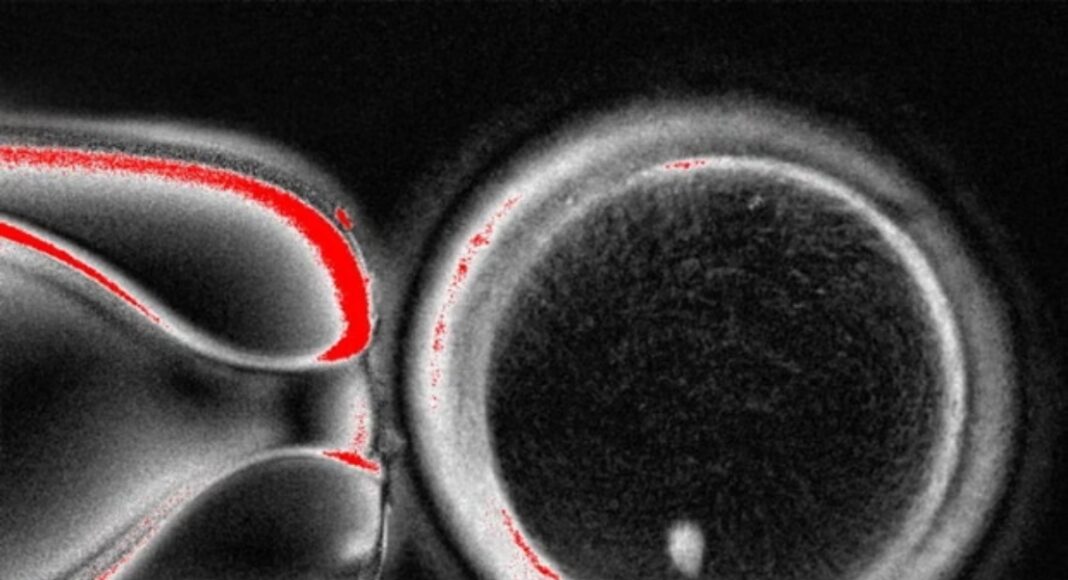

Η ομάδα του Όρεγκον ακολούθησε παρόμοια προσέγγιση, συλλέγοντας δερματικά κύτταρα από γυναίκες και αφαιρώντας τον πυρήνα από κάθε κύτταρο. Ο πυρήνας περιέχει τα 46 χρωμοσώματα που φέρουν περίπου 20.000 γονίδια που αποτελούν τον ανθρώπινο γενετικό κώδικα. Κάθε πυρήνας δερματικού κυττάρου τοποθετήθηκε σε ένα υγιές ωάριο δότη, του οποίου ο δικός του πυρήνας είχε αφαιρεθεί.

Η μεγαλύτερη πρόκληση για τους επιστήμονες ήταν ότι τα υγιή ανθρώπινα ωάρια περιέχουν μόνο 23 χρωμοσώματα. Τα υπόλοιπα 23 χρωμοσώματα προέρχονται από το σπέρμα κατά τη γονιμοποίηση και είναι απαραίτητα για να αναπτυχθεί το γονιμοποιημένο ωάριο σε έμβρυο και τελικά σε μωρό.

Σε άρθρο της που δημοσιεύθηκε στο επιστημονικό περιοδικό Nature Communications, η ερευνητική ομάδα περιγράφει πώς ξεπέρασε το πρόβλημα των χρωμοσωμάτων. Μετά τη γονιμοποίηση των ωαρίων με σπέρμα, τα ενεργοποίησαν χρησιμοποιώντας μια ένωση που ονομάζεται ροσκοβιτίνη. Αυτό είχε ως αποτέλεσμα τα ωάρια να μεταφέρουν περίπου τα μισά από τα χρωμοσώματά τους σε μια δομή που ονομάζεται πολικό σωμάτιο, αφήνοντας τα υπόλοιπα χρωμοσώματα να ζευγαρώσουν με αυτά του σπέρματος.

Σε ένα υγιές γονιμοποιημένο ανθρώπινο ωάριο, τα 23 χρωμοσώματα της μητέρας συνδυάζονται με τα 23 του πατέρα. Ωστόσο, η ομάδα διαπίστωσε ότι τα χρωμοσώματα στα ωάριά τους διαχωρίζονταν και συνδυάζονταν τυχαία. Αυτό οδήγησε σε έμβρυα πρώιμου σταδίου με λανθασμένο αριθμό χρωμοσωμάτων και λανθασμένους συνδυασμούς χρωμοσωμάτων.

Από τα 82 ωάρια που δημιουργήθηκαν στο εργαστήριο του Όρεγκον, λιγότερα από 10% αναπτύχθηκαν στο στάδιο όπου τα έμβρυα εξωσωματικής γονιμοποίησης μεταφέρονται συνήθως στη μήτρα, γεγονός που υποδηλώνει ότι η διαδικασία δεν είναι ιδιαίτερα αποτελεσματική. Κανένα από αυτά δεν καλλιεργήθηκε πέραν των έξι ημερών.